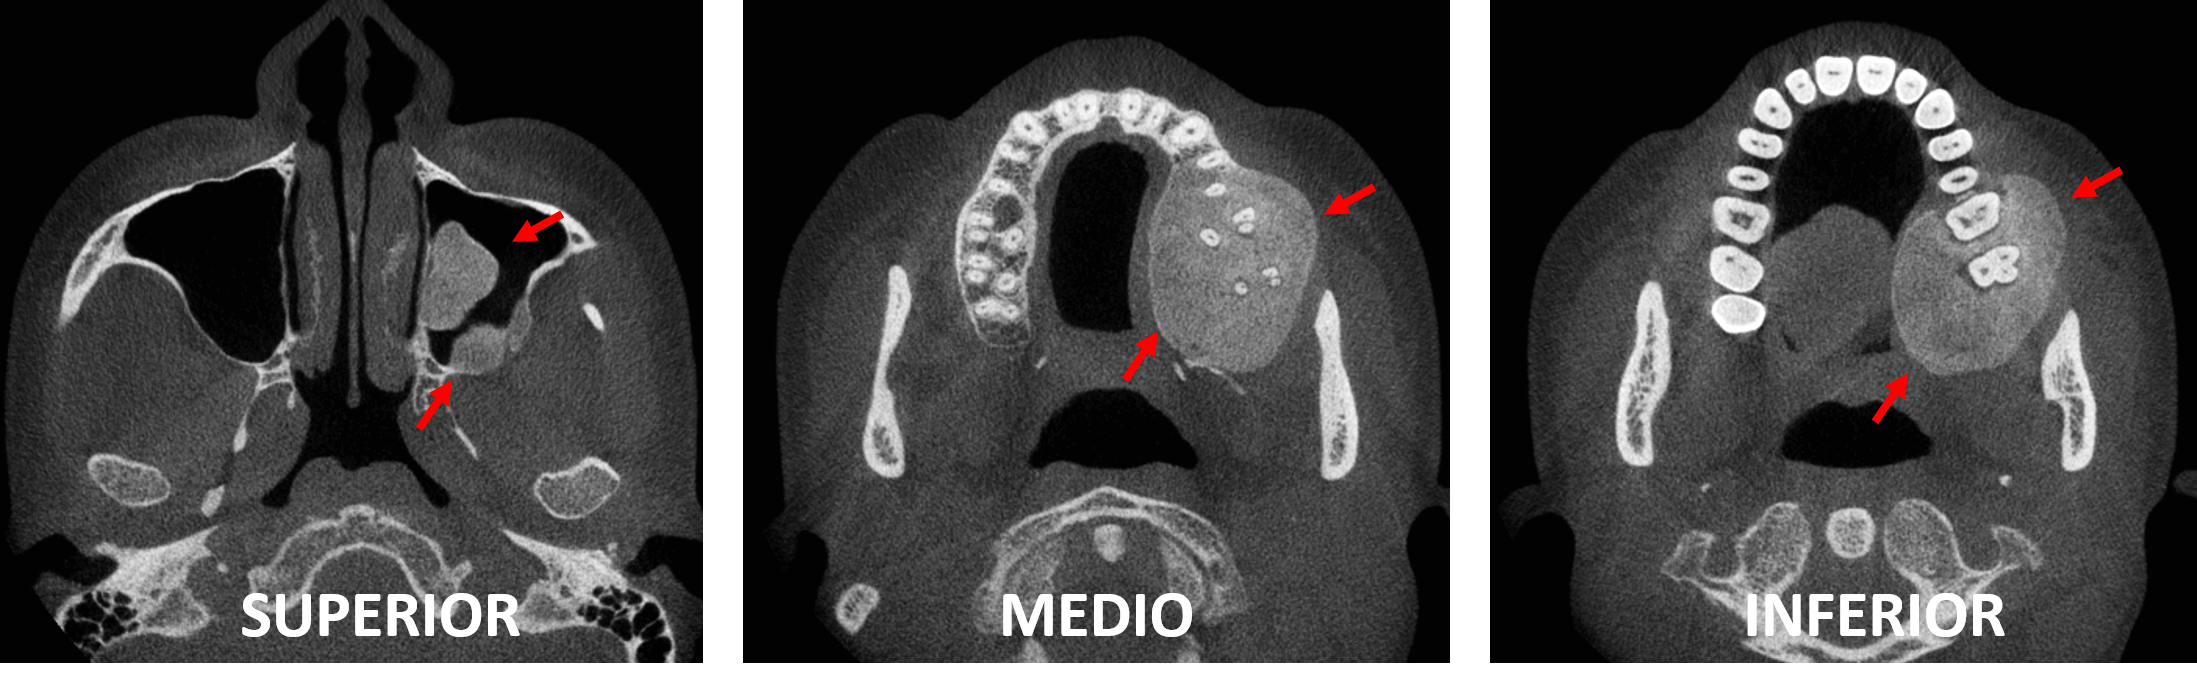

Fig.4

En la reconstrucción tridimensional (Fig.4) se observa el tamaño de la lesion ósea, donde se observa condicionando una marcada asimetría del hueso maxilar.